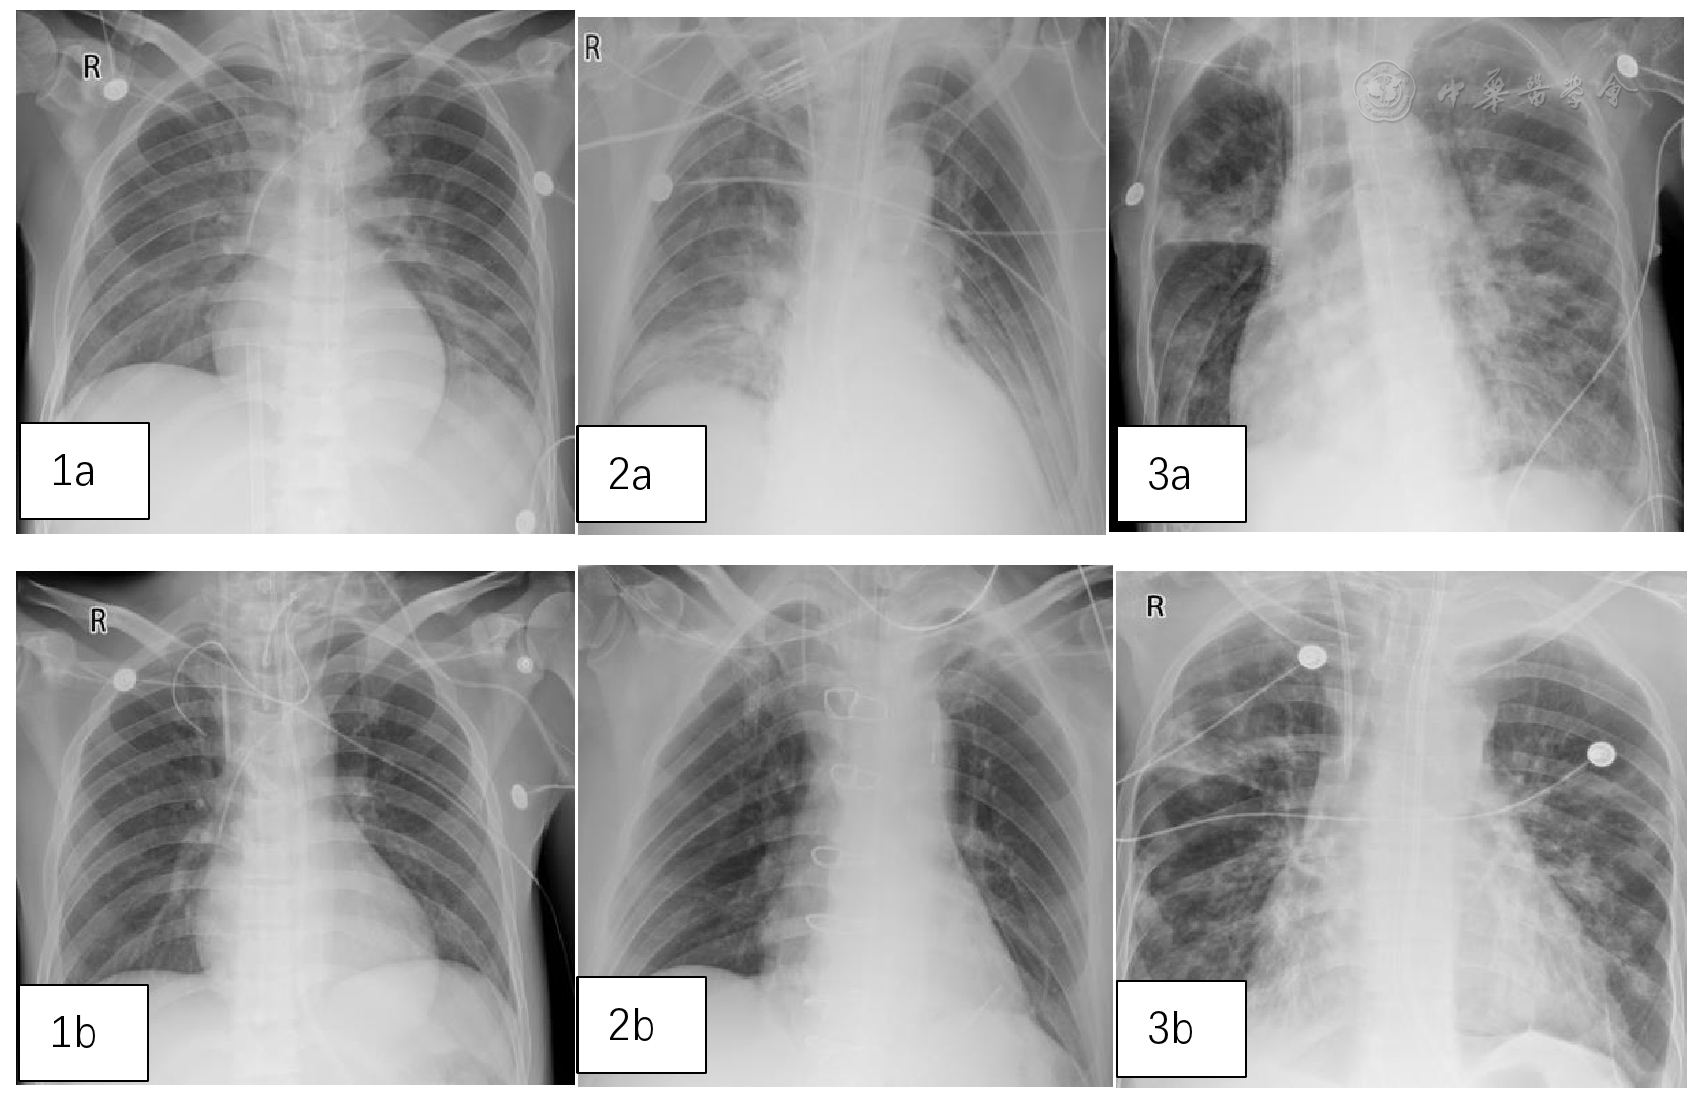

图1 3例患者治疗前后肺部影像学对比。图1a、2a、3a分别为病例1、2、3治疗前,图1b、2b、3b分别为病例1、2、3治疗2周后

3例患者均为男性,年龄38~58岁,分别在肺泡灌洗液、血液中检出鲍曼不动杆菌,药敏试验结果均提示对碳青霉烯类抗生素耐药。依拉环素治疗后患者临床表现、炎症指标及影像学检查均明显好转,且未发现依拉环素治疗相关不良反应。

All three patients were male, aged 38-58 years. Acinetobacter baumannii was detected in bronchoalveolar lavage fluid and blood cultures, with susceptibility testing indicating resistance to carbapenem antibiotics. After treatment of Eravacycline, significant improvements were observed in clinical manifestations, inflammatory indicators, and imaging examinations. No Eravacycline-related adverse reactions were identified.